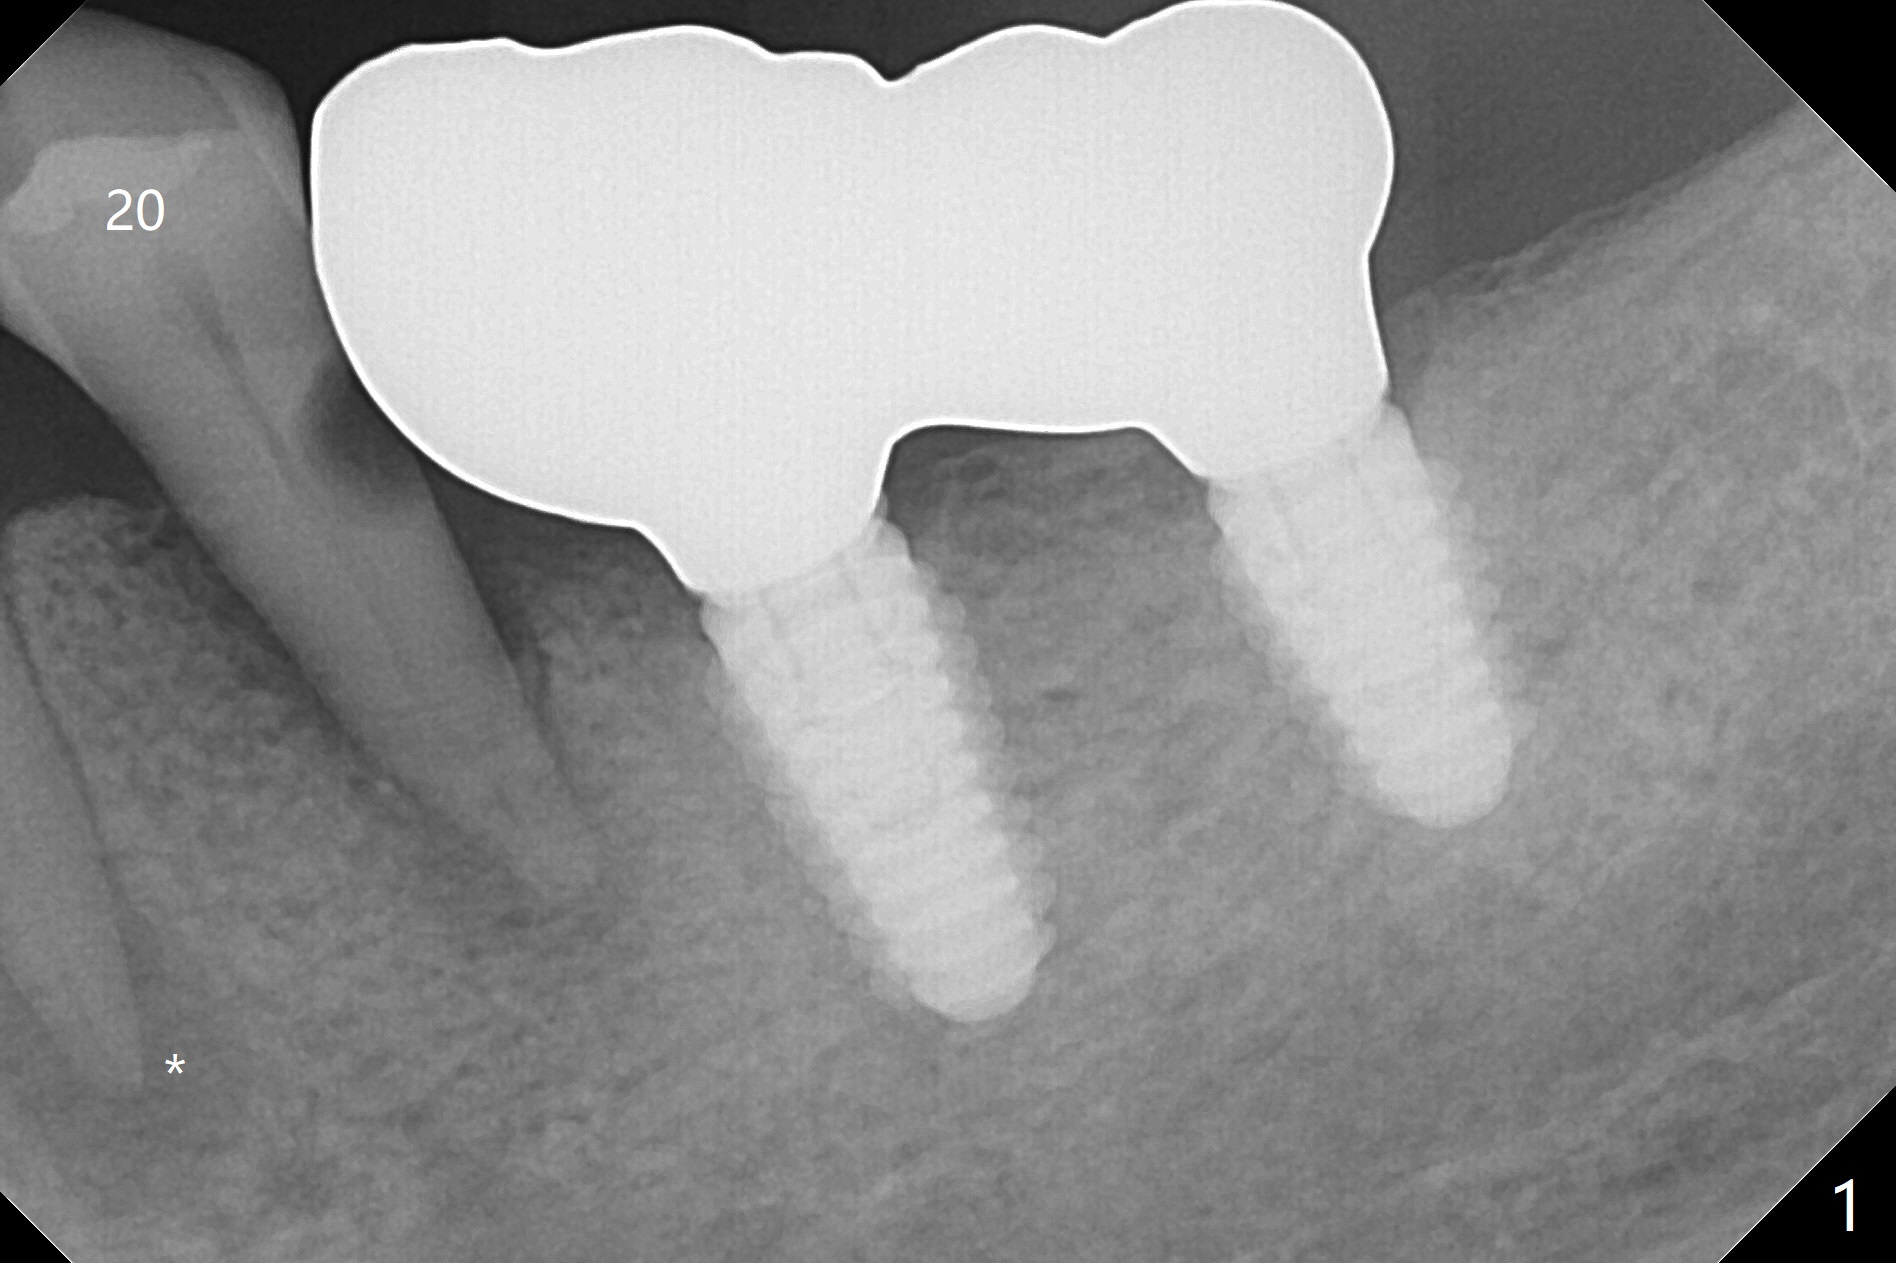

A 73-year-old man with history of stroke presented to office with #20 chewing pain 2 years ago (Fig.1). When he returns today, the tooth #20 has lost, while #21 has mobility (Fig.2), torus mandibularis (Fig.3 *) and severe bone loss, as related to Class V defect (Fig.4). As expected, the buccal plate is lost, the buccal gingiva blanching and bulging due to a curette underneath (Fig.5 *). After placement of allograft in the socket (Fig.6,8 *), a 8x8 mm BioXclude and 4-0 PGA suture are used to close the socket (Fig.7). Periodontal dressing stays in place 10 days postop (Fig.9). The patient is pleased with hemostasis. He is going to return his home state.